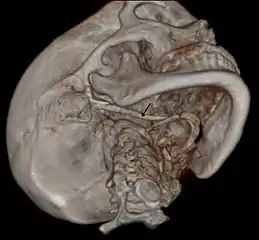

3D-reconstructed CT scan showing bilateral stylohyoid ligament ossification

3D reconstructed CT scan showing elongated styloid process (right side)

Imaging is important and is diagnostic. Visualizing the styloid process on a CT scan with 3D reconstruction is the suggested imaging technique.[12] The enlarged styloid may be visible on an orthopantogram or a lateral soft tissue X ray of the neck.